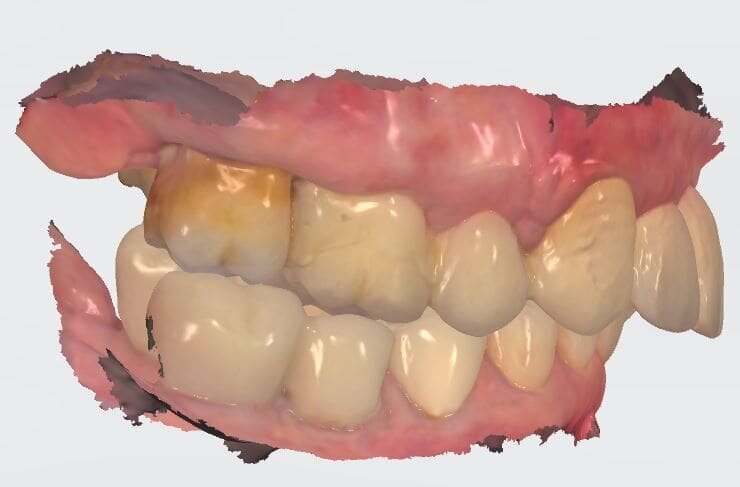

L’informazione diagnostica dettagliata è fornita dalla CBCT, pertanto abbiamo pianificato la sua esecuzione dopo la prima provvisorizzazione dell’arcata superiore evitando lo scattering da metalli presenti. Il file STL del wax-up (Fig. 6) associato al file STL dell’impronta senza provvisorio (Fig. 7) e al file DICOM radiologico (Figg. 8, 9) ha permesso una corretta progettazione chirurgico implantare (Fig. 10) nel rispetto della porzione ossea della cresta residua, ottimizzando la conseguente realizzazione della dima chirurgica (Fig. 11) per il posizionamento degli impianti in sede 1.2 e 2.2 (Figg. 12-14) anche nel rispetto della posizione degli elementi in antagonismo (Fig. 15). Il primo provvisorio avrà diverse funzioni tra cui la valutazione dell’inclinazione coronale, l’ingombro volumetrico e il supporto labiale del gruppo frontale per la correzione dell’emergenza del labbro superiore (Fig. 16). Dopo un breve periodo di stabilizzazione funzionale di almeno due mesi, si valutano i movimenti mandibolari, masticatori, il ripristino dei tessuti parodontali e il condizionamento biologico degli elementi intermedi. Nello specifico del caso trattato abbiamo evidenziato subito un collasso della masticazione associato a un morso profondo che non avrebbe consentito alcuna protesizzazione degli elementi mancanti (Fig. 2). Pertanto abbiamo dovuto realizzare un rialzo di masticazione anche per correggere l’emergenza degli elementi sostitutivi. La preparazione degli elementi residui concepita ha eliminato tutti i materiali che avrebbero creato un disturbo nell’indagine radiologica (Fig. 17).

I dati raccolti sono molti ma la procedura digitale consente di sommarli e confrontarli senza limiti e indicando le possibili migliori e correzioni lungo il percorso. Dopo un breve periodo di condizionamento dei tessuti (Fig. 30) rileviamo l’impronta master per la finalizzazione ultima della riabilitazione protesica. L’impronta degli elementi naturali viene rilevata posizionando dei fili detrattori secondo la tecnica del doppio filo mentre per gli impianti verranno usati gli scan body dedicati (Fig. 31). Le potenzialità digitali consentiranno di avere una stabile lettura della posizione di centrica rilevandola prima della rimozione dei provvisori e sovrapponendola a provvisori rimossi (Fig. 32). In laboratorio l’odontotecnico realizza i modelli (Figg. 33, 34) sovrappone le immagini (Fig. 35) e raccoglie gli elaborati dei vari passaggi che porteranno alla finalizzazione del progetto digitale (Figg. 36, 37). Gli impianti in Zirconia non offrono molte soluzioni protesiche, è importante che il loro posizionamento tenga conto di quest’aspetto mettendo l’odontotecnico nelle condizioni più favorevoli (Fig. 38). Questa sistematica prevede l’uso di un moncone in titanio cementato nella struttura protesica che permette l’avvitamento all’interno dell’impianto. Nella connessione implantare è presente un’intercapedine dove alloggia il collarino in titanio del T-base totalmente inglobato all’interno della zirconia, evitando comunicazioni coi tessuti adiacenti. Va comunque considerato l’aspetto tecnico importante legato allo spessore della struttura in zirconia che deve avvolgere l’intero moncone in titanio. (Fig. 39, 40).